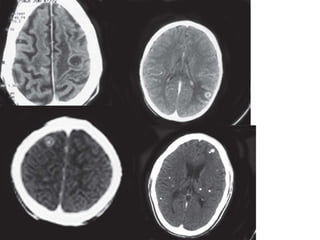

CECT axial scans of the cranium showing dense meningeal enhancement along the basal

cisterns, tentorium and the sylvian

cisterns with evidence of hydrocephalus and periventricular ooze — tubercular meningitis

CT

• Computed tomography shows obliteration by

isoattenuating or marginally hyperattenuating exudate

at the basal cisterns and plaque like dural thickening

• On intravenous contrast administration, there is dense

homogeneous enhancement of the basal cisterns

which may extend to the convexities, tentorium and

sylvian fissures

• ependymitis is seen as a linear enhancement along the

ventricular margins.

• The presence of hydrocephalus is thought to be related

to poor prognosis.